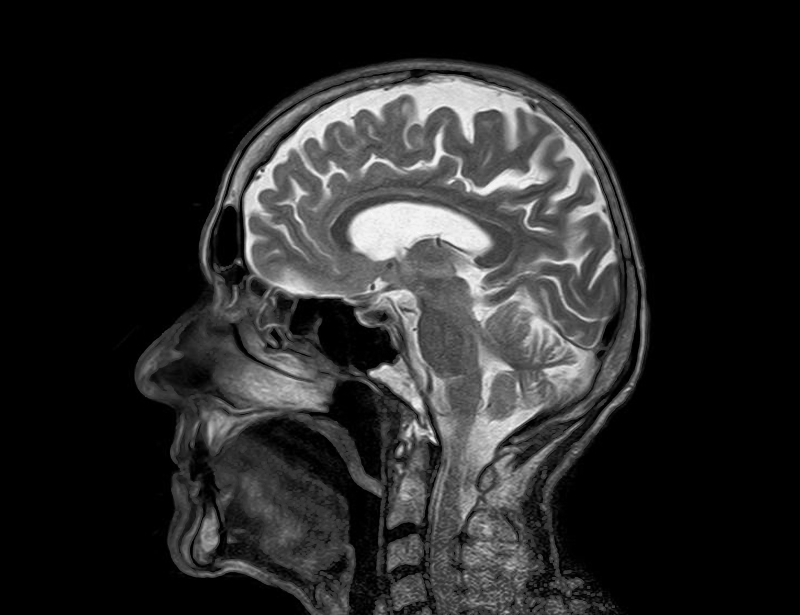

Ovo je postignuto na taj način da su testni subjekti ležali u stroju za MRI skeniranje, a pritom im nije rečeno da trebaju zamisliti bilo što određeno.

Proces "usađivanja" je trajao nekoliko dana, a na početku su subjektima skenirali mozgove s ciljem da softver nauči koje vrste moždanih aktivnosti treba pratiti, da bi nakon toga subjekti subjeki tri dana prolazili osnovni neurofeedback trening.